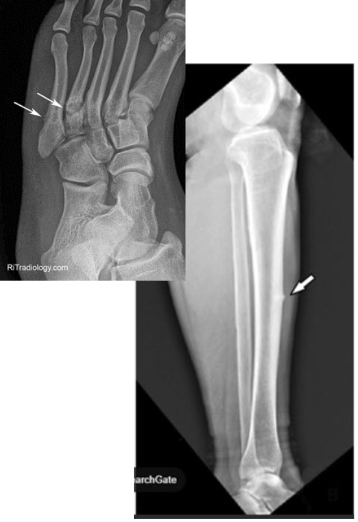

What type of fracture is this?

Avulsion

What is an avulsion fracture?

Fragment of bone is pulled away an attached tendon or ligament

Chip

What is a chip fracture?

Isolated bone fragment NOT caused by tendon or ligament